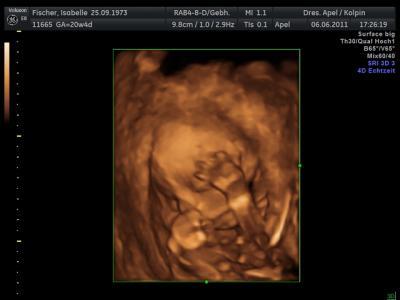

so ich bin dann auch mal wieder zurück von meinem Termin alle Werte in Ordnung Outing immer noch bei 60% aber hab ja morgen FD da wirds sicher 100% mein Schäfchen wiegt ca. 340g, wie groß es ist hat sie leider nicht gesagt diesmal hats geschlafen beim Ultraschall Nabelschnur war auch immer vorm Gesicht aber finde die Bilder trotzdem schön

Bild zu zurück vom FA - Forum für Oktober - Mamis